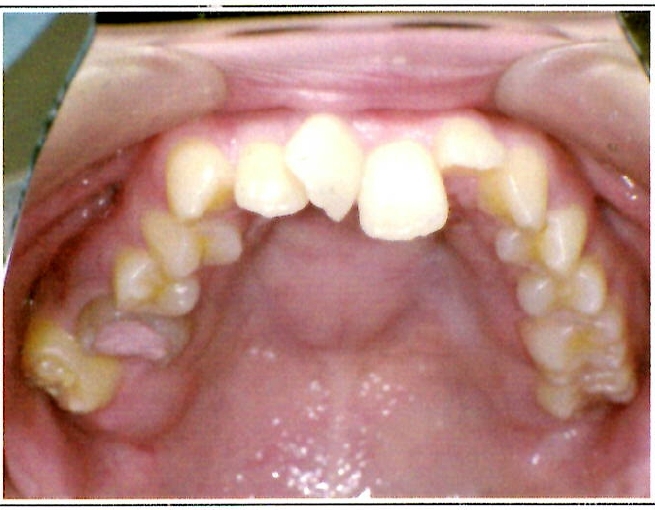

| 主訴・治療前の状態 | 著しい叢生(歯並びのガタガタ)があり、また6歳臼歯(第一大臼歯)が破折していた状態でした。 |

| 治療内容 | 通常の抜歯矯正では第一小臼歯(4番)を抜歯することが多く、その方が治療期間を短縮できますが、小川さんの場合は破折していた6歳臼歯を抜歯し、そのスペースを活用して歯列を整えました。これにより、健康な歯の本数を維持しながら矯正治療を行うことができました。 |

| 治療結果 | 治療前と比較して歯並びが大きく改善し、見た目も大幅に良くなりました。患者様にも大変喜んでいただけた症例です。 |